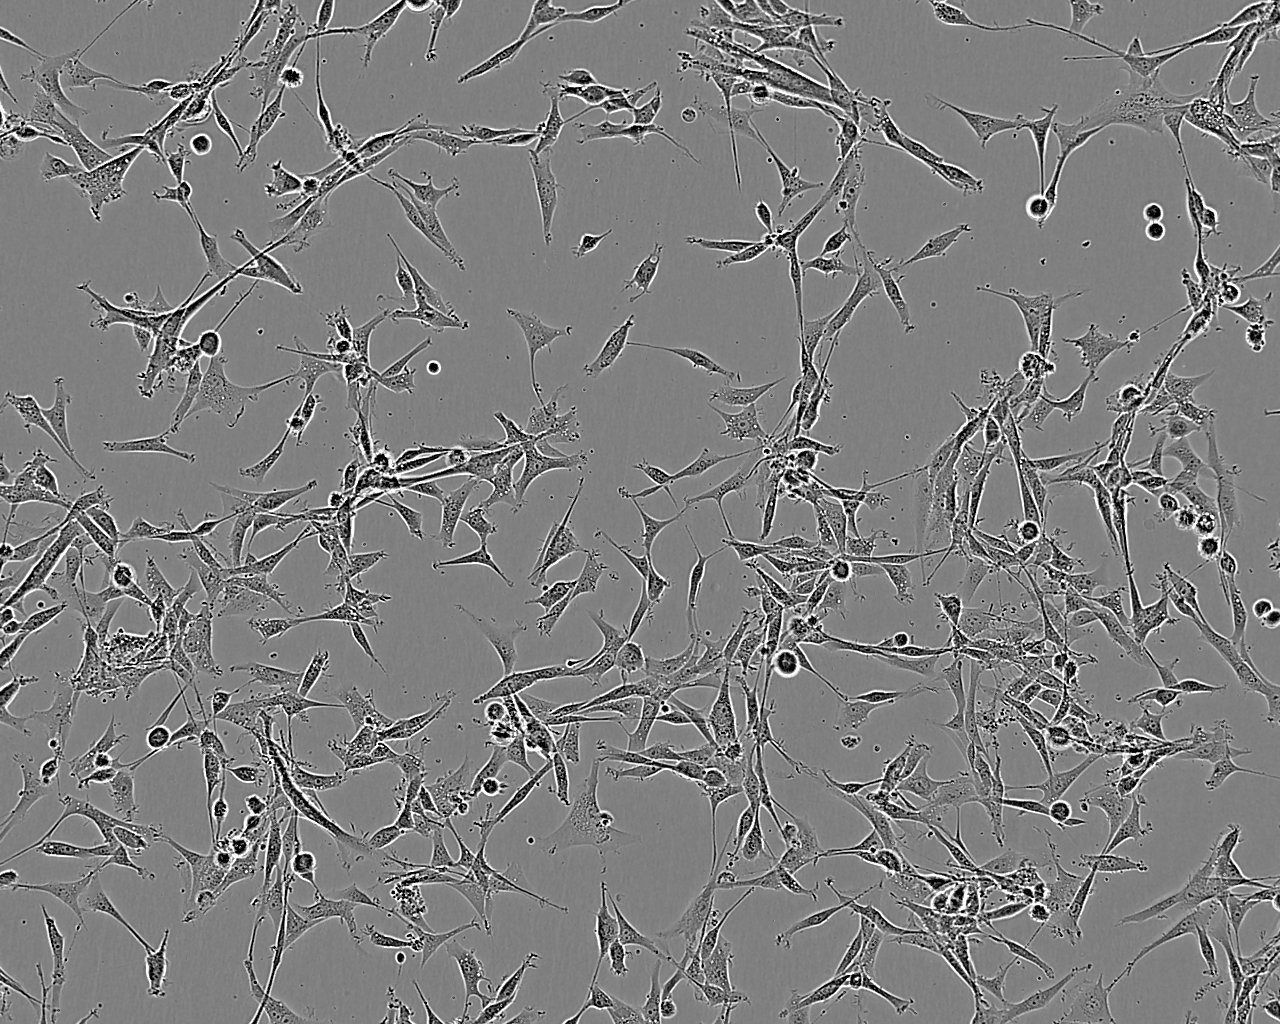

细胞形态:上皮细胞样

细胞生长:贴壁

细胞生长特性:贴壁生长